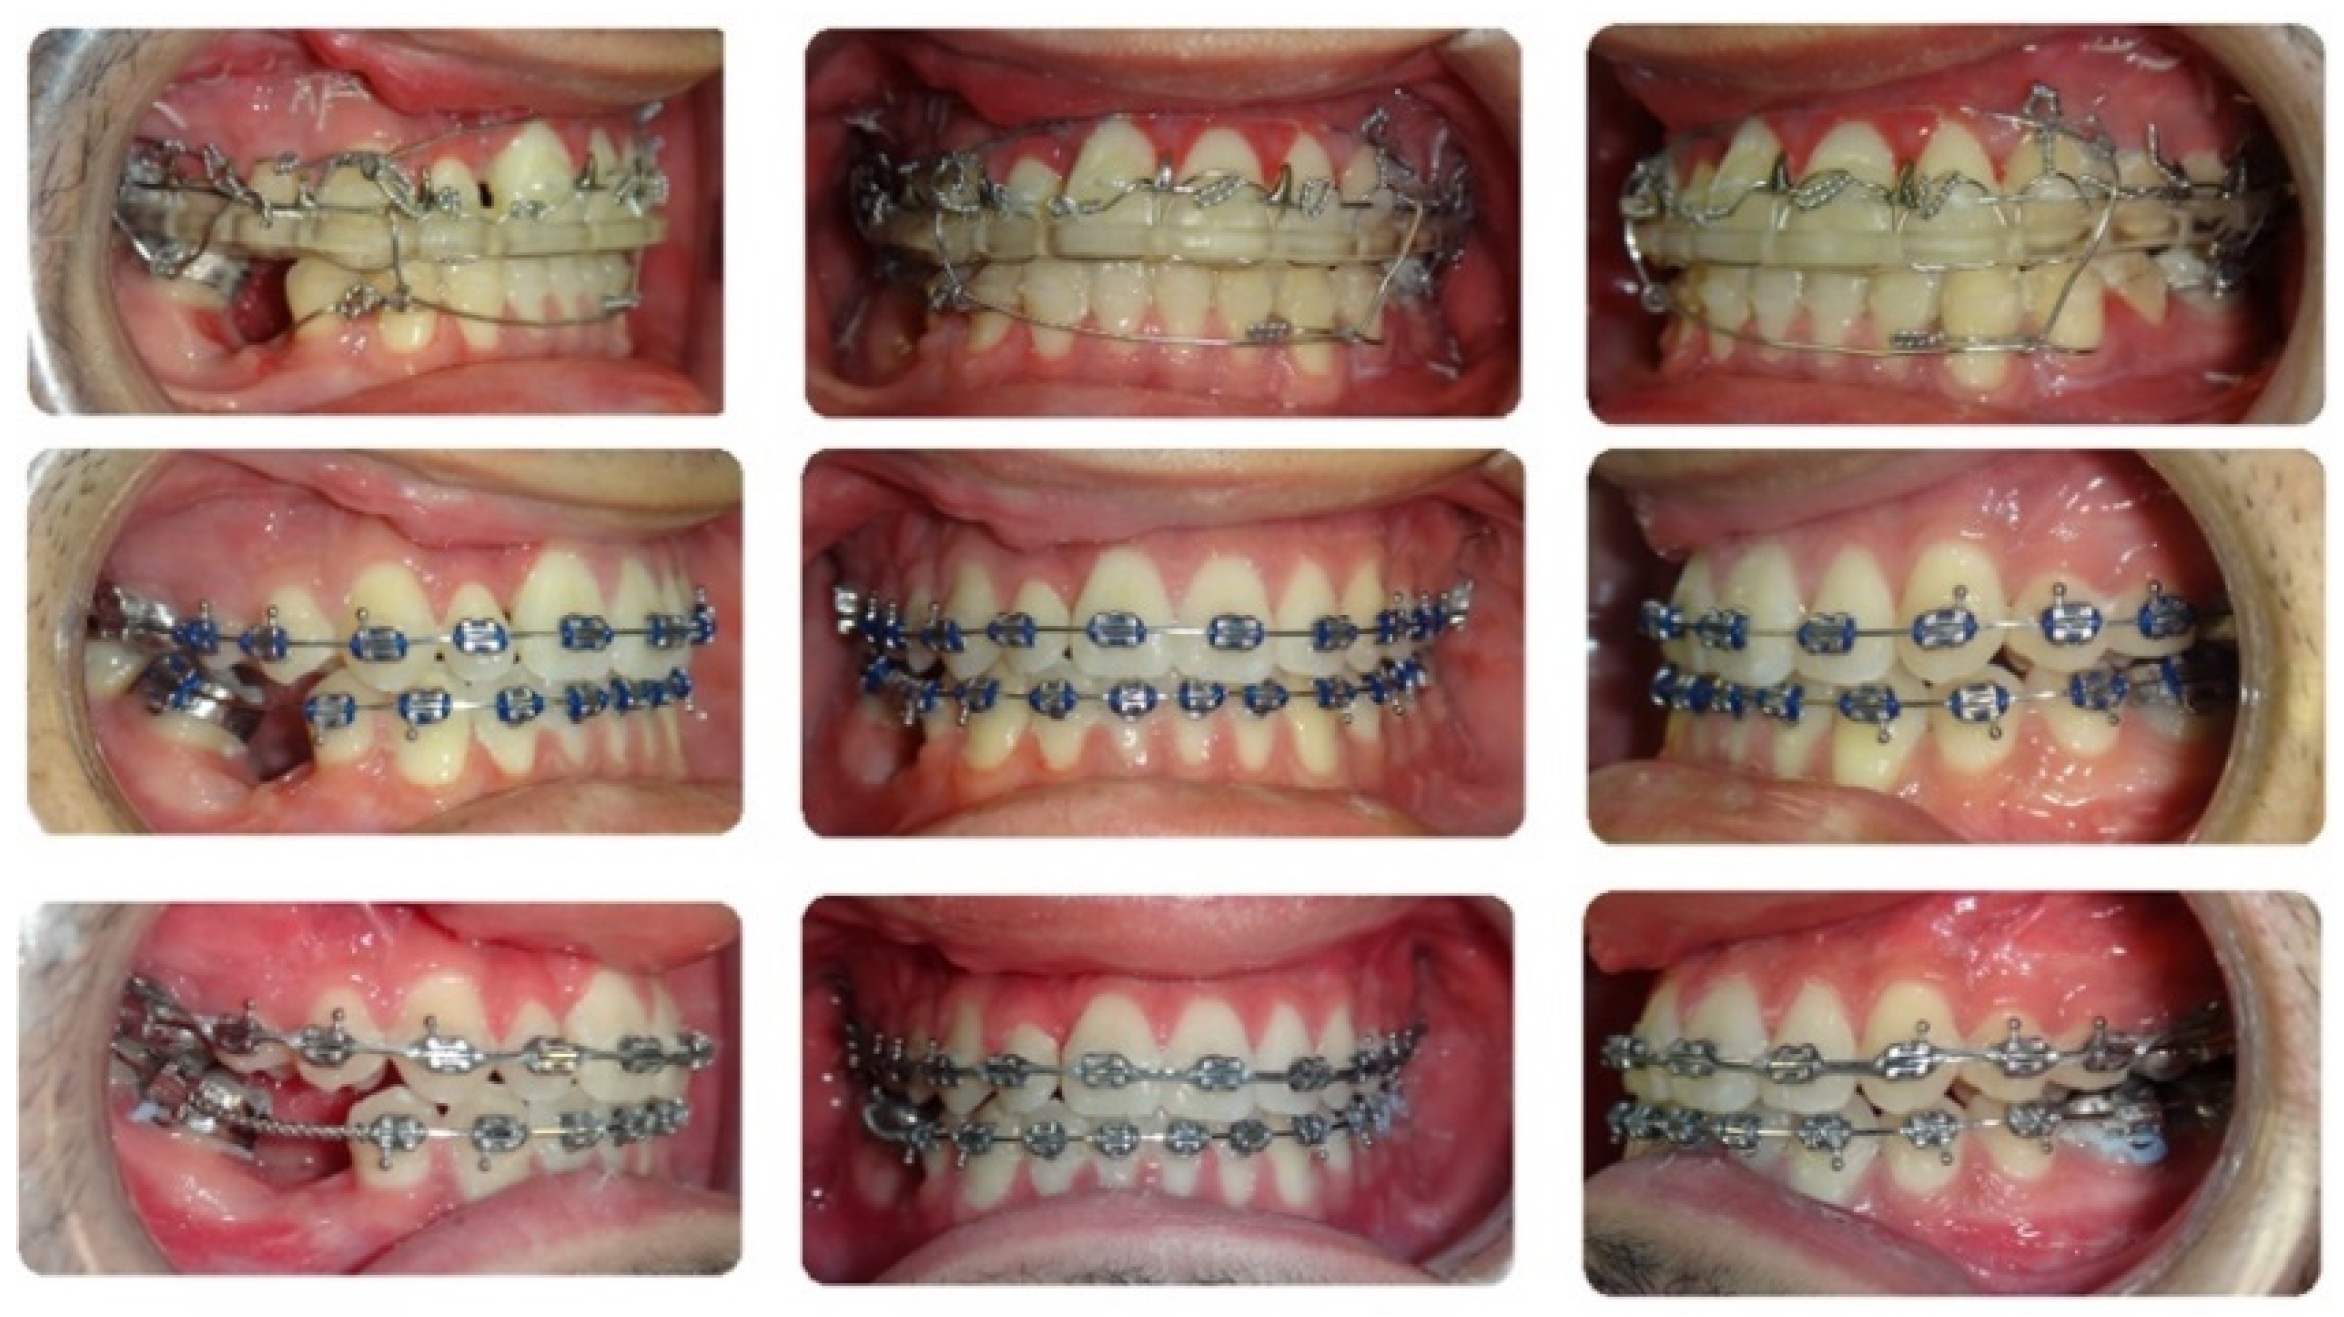

2. Case Description

3.3. Step 3: Reverse Engineering the Transitional Occlusion